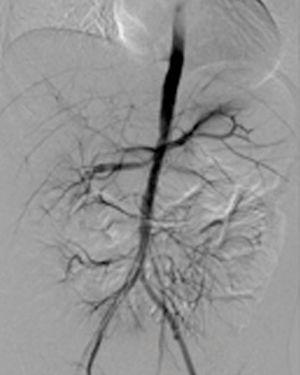

Another arteriography was performed, which reported irregular abdominal aorta with progressive distal thinning, arterial anastomosis autotransplant occlusion and progression of right renal artery stenosis (Figure 2); it was decided that a right renal primary angioplasty was to be carried out, which was unsuccessful due to the persistence of stenosis. Because of the difficult monitoring of blood pressure figures, selective venous sampling of the renal veins was performed to measure renin, with a difference of 10:1 being found in the concentrations of autotransplanted kidney against the right kidney. This confirmed the suspicion of renovascular HBP originating in the autotransplanted kidney. It was not possible to perform autotransplanted renal artery embolisation due to the risk of extensive necrosis, as parasitic branches were found that provided flow to the autotransplanted kidney and the intrinsic muscles of the pelvis. It was decided to carry out nephrectomy of the left autotransplant. Evolution was satisfactory with better control of blood pressure figures, and as such, the patient was discharged.

Figure 2. Abdominal arteriography